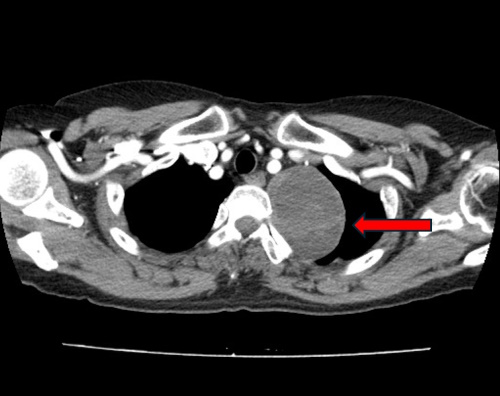

▲ 종격동 종양 환자의 흉부 CT 사진.